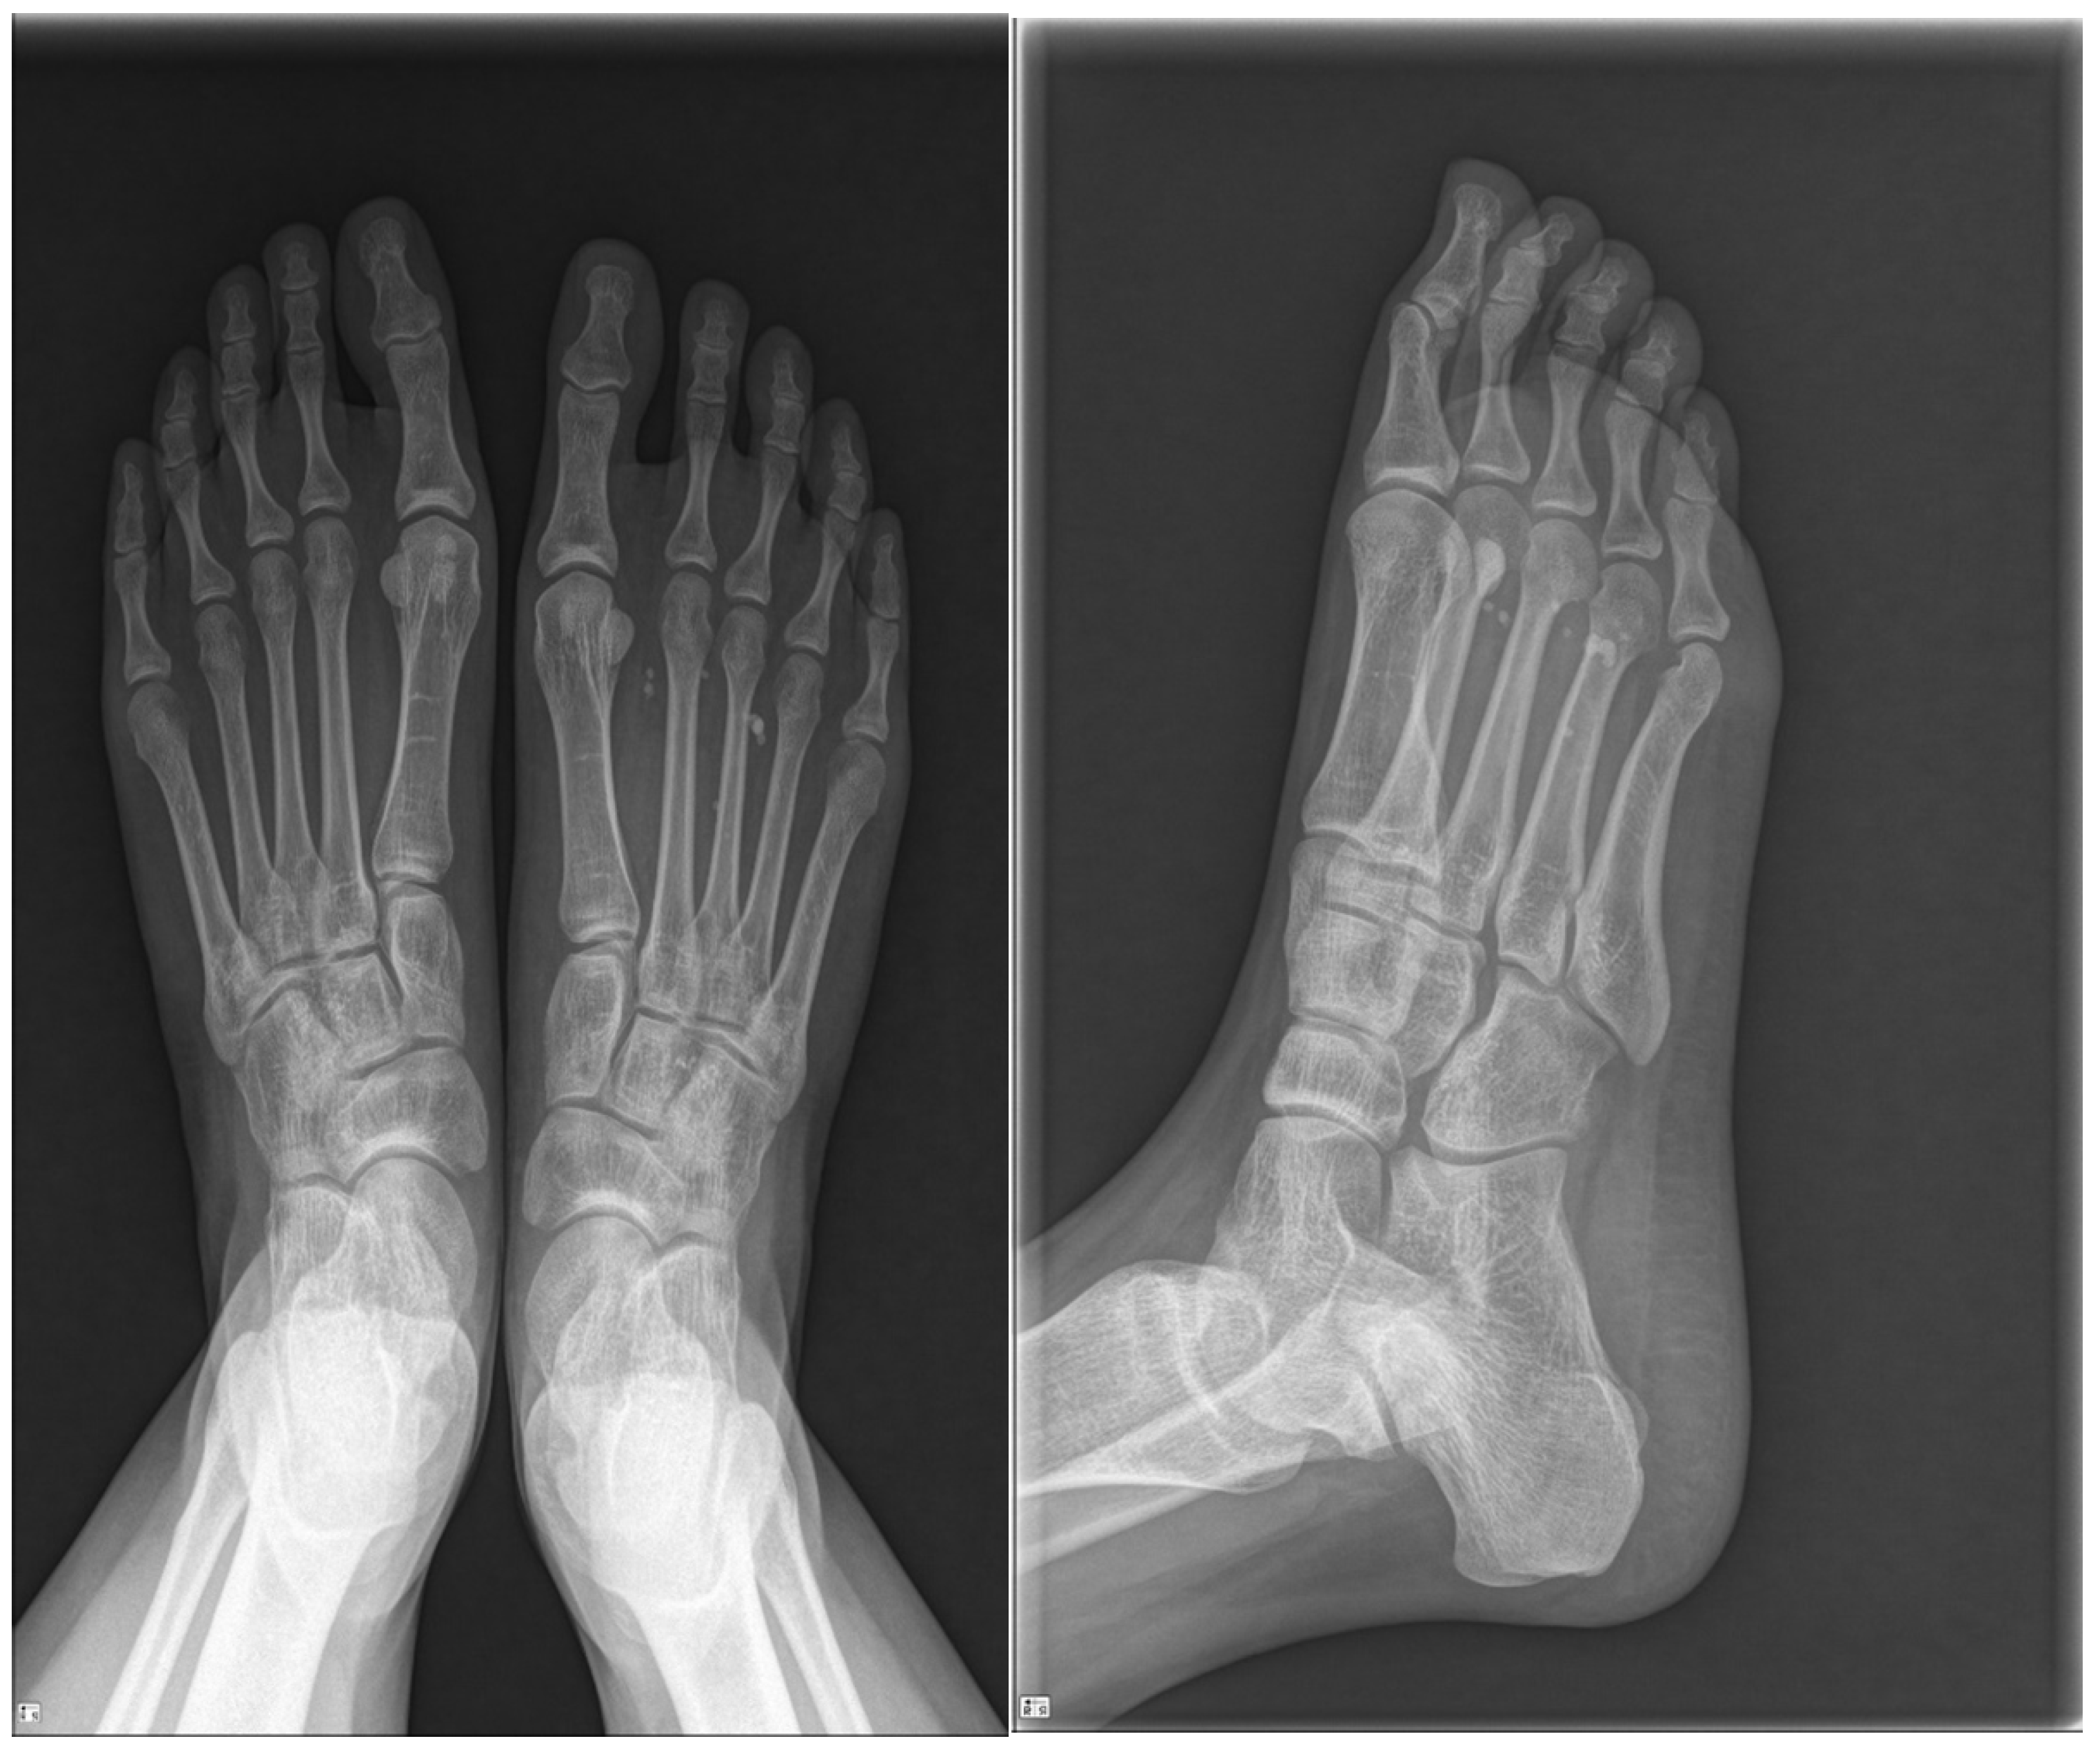

2.1. Preoperative Evaluation